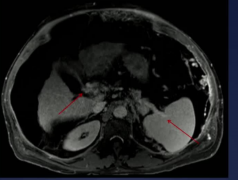

• [门静脉血栓影像学诊断] 内脏静脉血栓的影像学 日期:2025-10-07 06:04:34 点击:99